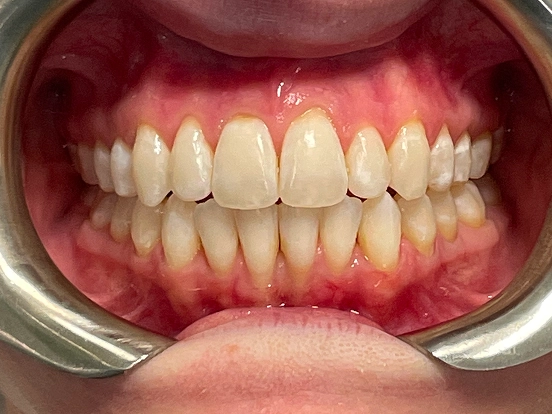

Invisalign CK

This Invisalign case shows how clear aligners can completely transform a smile without the need for metal braces. Over the course of treatment, CK achieved a beautifully aligned smile with improved symmetry and confidence. The results highlight how Invisalign offers both comfort and precision for a stunning new look.